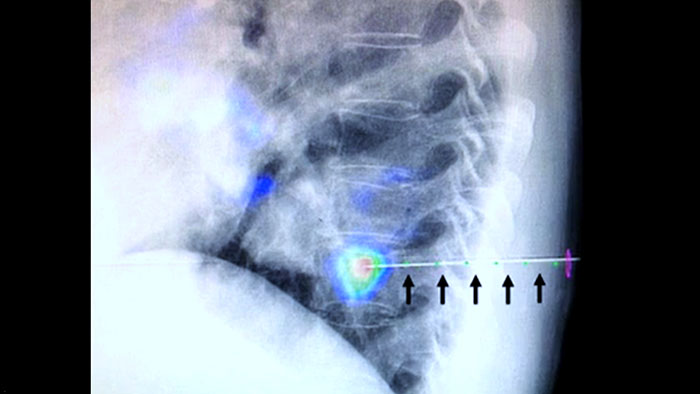

Технология XperGuide обеспечивает точный визуальный контроль при ведении иглы к исследуемой области в режиме реального времени, накладывая изображения предварительно запланированной траектории на рентгеноскопические изображения3.

Неоднородность поражения и плохие пределы видимости снижают качество взятых проб и возможность выполнения биопсии под контролем УЗИ или стандартной КТ. Распространение программ скрининга легких поспособствовало увеличению частоты обнаружения ранних форм рака легких, проявляющихся в виде небольших узелков. У 14,5% обследованных были обнаружены узелки размером ≤ 10 мм1-2. Наша технология навигации иглы и КТ-подобные изображения повышают точность работы и позволяют выделить поражения меньшего размера (<=1 см) либо гетерогенные поражения, а также минимизируют количество процедур повторного позиционирования иглы и позволяют использовать меньшую дозу в сравнении с традиционной КТ1-2.